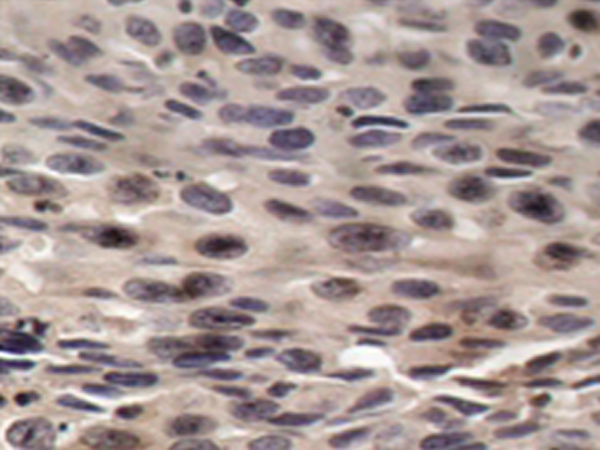

IHC positive control: |

Human breast carcinoma tissue; |

IHC Recommend dilution: |

50-100 |